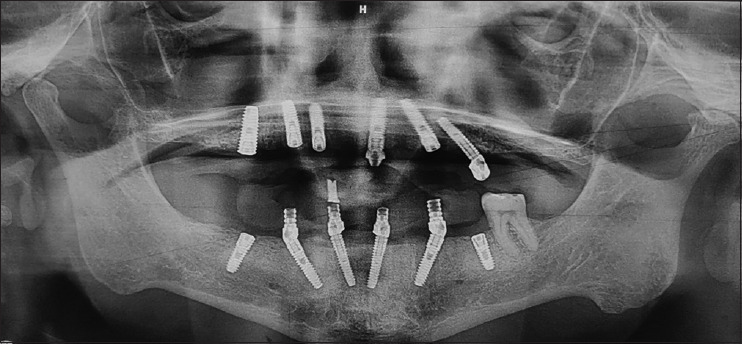

Aim: The aim of this study was to evaluate immediately loaded implants, both clinically and radiographically, in extraction sites (IPIL) and healed sites (HSIL), rehabilitated using All-on-4/All-on-6 protocol, over a time span of 2 years.

Materials and methods: A total of 15 patients were evaluated, in 2 years, for study purpose. Among 87 immediately loaded implants, 44 were IPIL and 43 were HSIL. The bone level was measured using Implant abutment junction as reference point, at 0, 6, 12, 18 and 24 months. Bone loss was calculated as difference of mean.

Results: The average bone loss for 2 years was 1.39 mm and 1.17 mm, in IPIL and HSIL group respectively with 100% implant survival rate and no statistical difference (P < 0.05).

Conclusion: Full arch prostheses can be successfully delivered by immediate loading of implants regardless of placement (healed or extraction sites).